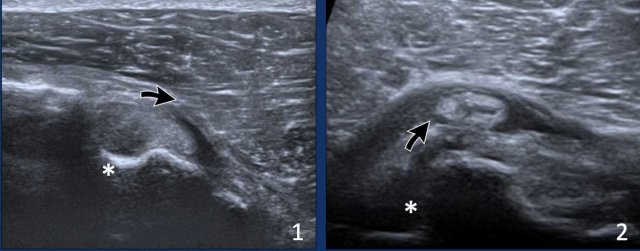

Images

1. Eccentric position of the long head of the biceps tendon due to laxity of the biceps pulley.

2. Dislocation of the biceps tendon. Notice the empty bicipital groove (asterix)